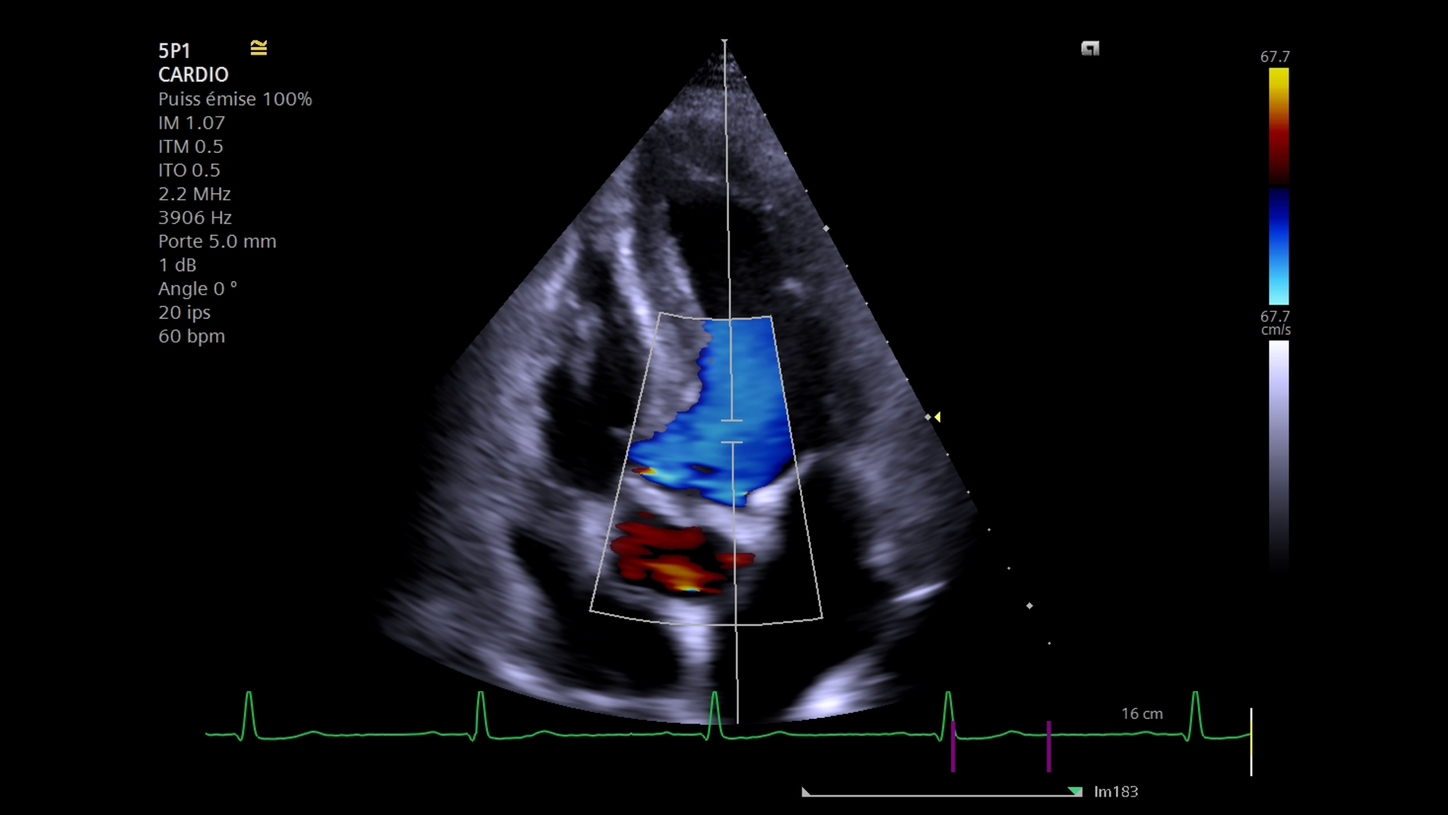

Rétrécissement aortique calcifié : écho-Doppler transthoracique

L'échocardiographie Doppler demeure la pierre angulaire du diagnostic et de la quantification du RAC. Les principales étapes de l’examen sont l'évaluation du degré de calcification valvulaire aortique, la mesure des diamètres de l’anneau sous-valvulaire et de l'aorte initiale, le calcul des gradients transvalvulaires et l’évaluation de la fonction ventriculaire gauche. Les outils de quantification automatisés ont toute leur place, notamment pour l’analyse des flux Doppler et la fonction ventriculaire gauche (fraction d’éjection, strain), sachant que les indications opératoires sont basées sur cette analyse

Au travers de ce poster, le Professeur Jean-Luc Monin, cardiologue au sein de l'Institut Montsouris à Paris, vous livre sa méthodologie et ses astuces en y intégrant les outils d'intelligence artificielle disponibles sur l'échographe ACUSON Juniper.